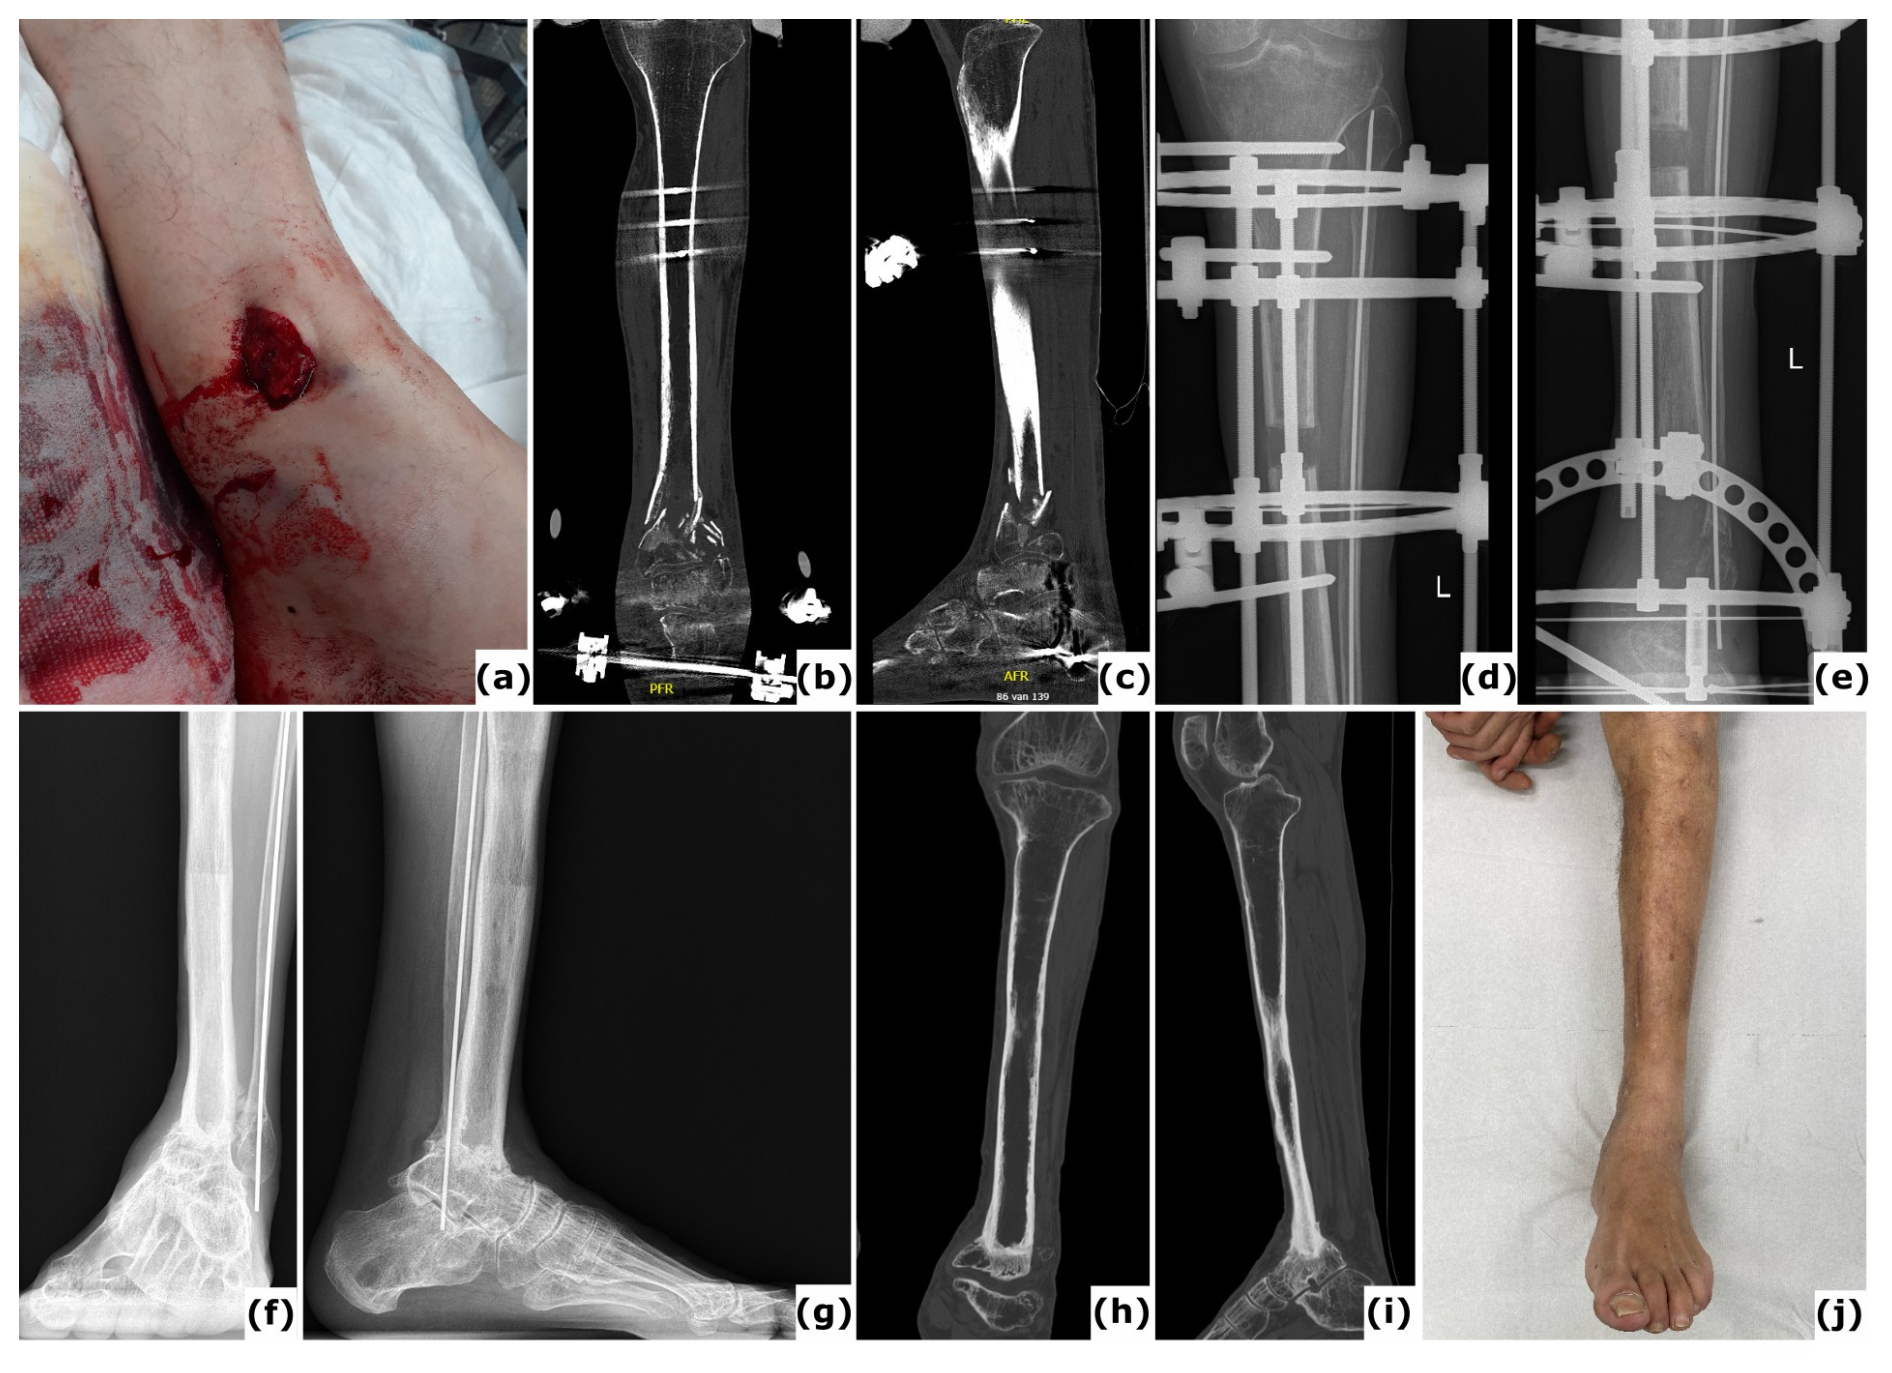

Figure 7Bone transport nail. (a) Anteroposterior radiograph of a 26-year-old patient with a Gustilo-Anderson type III open tibia and fibula fracture, including 95 mm bone loss. In the initial surgery, a temporary PMMA spacer was placed at the defect site and the bone ends were prepared for bone transport. Provisional fixation was achieved using initial hybrid spanning fixation and an intramedullary wire in the fibula. (b–c) Anteroposterior and lateral radiographs display application of a bone transport nail with proximal and distal locking pegs, and required poller screw fixation to minimize drift during transport. (d) Anteroposterior radiograph demonstrates regenerate formation after a 2-week latency period and distraction at 0.6 mm d−1. (e–f) Anteroposterior and lateral radiographs document progressive healing subsequent to open docking. (g–h) Anteroposterior and lateral radiographs indicate solid and mature healing following removal of the bone transport nail 2 years post-injury.